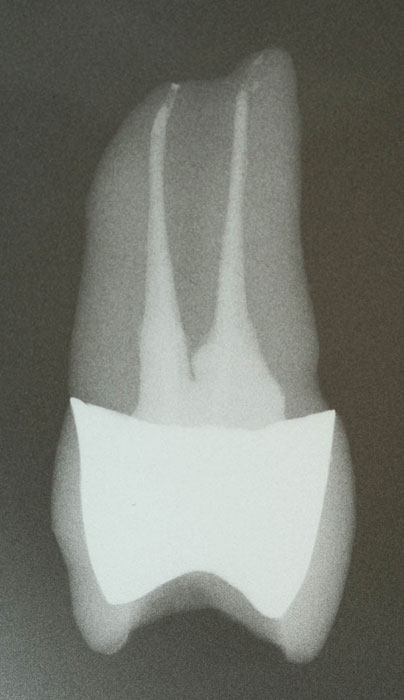

Oberer zweiter Prämolar mit zwei Wurzelkanälen und apikalen Ramifikationen als transparentes Präparat nach in-vitro-Behandlung

Die Pulpahohlräume waren vor der Behandlung violett angefärbt worden.

Dadurch sind nicht erfasste Wurzelkanalanteile deutlich erkennbar.

In den apikalen Anteil des palatinalen Wurzelkanals ist Sealer eingeflossen.

Das Röntgenbild zeigt deutlich, dass hier keine dichte Füllung vorliegt.